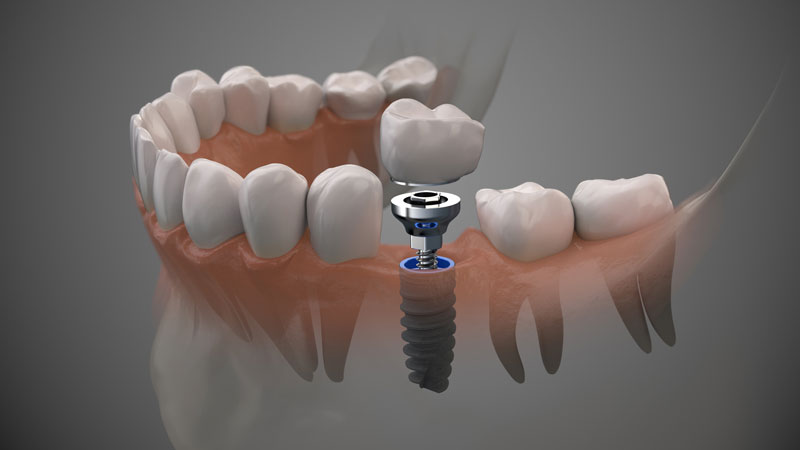

A Comprehensive Walkthrough of Stages of Dental Implants

The Strength in your Smile: Understanding the Role of the Tooth Post in Dental Implants

What Does The Dental Implant Post Part Of A Dental Implant Do?